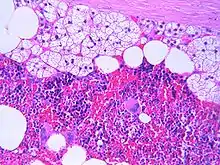

Microscopic features

The typical microscopic features of myelolipomas are shown in the image. There is a mixture of normal adrenal tissue, fat, and a full trilineage maturation of the three major blood-forming elements: myeloid (white blood cell forming), erythroid (red blood cell forming), and megakaryocytic (platelet forming) lines.[1]